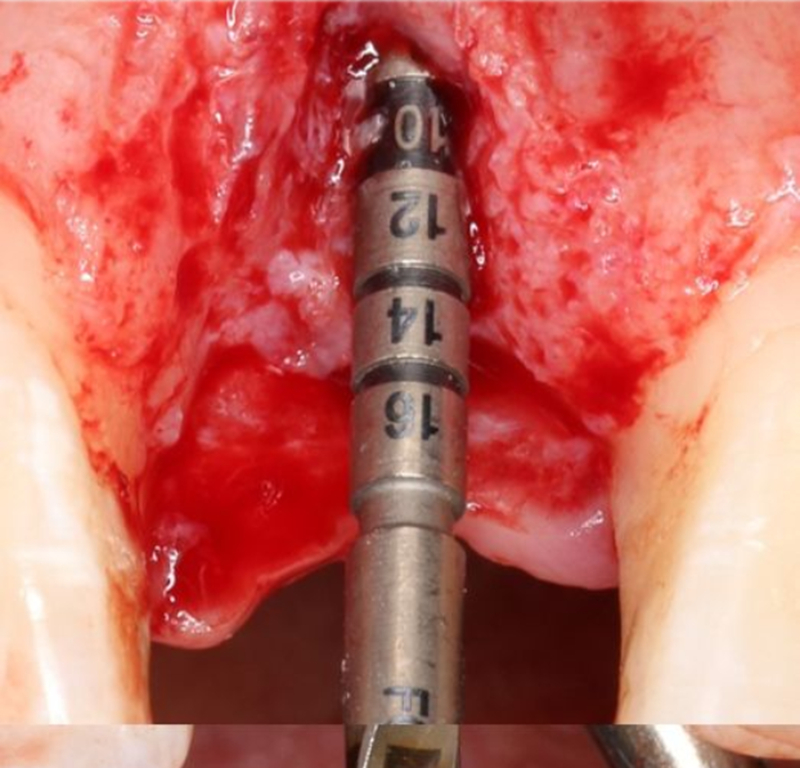

逐級擴孔

2.2mm 先鋒鉆確定植入深度及軸向

在實時導(dǎo)航系統(tǒng)中,實時引導(dǎo)先鋒鉆按照術(shù)前設(shè)計種植體軸向及深度進行擴孔

2.8mm 擴孔鉆按種植體軸向擴大窩洞

在實時導(dǎo)航系統(tǒng)中,實時引導(dǎo)擴孔鉆按照術(shù)前設(shè)計種植體軸向及深度進行擴孔